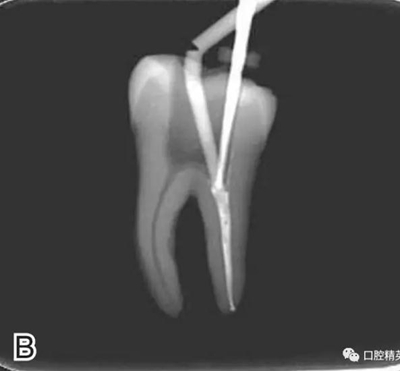

3、試尖

選擇非標(biāo)準(zhǔn)牙膠尖(如0.04、0.06 錐度牙膠尖)作為主尖,型號一般與根管預(yù)備最大號的器械型號一致,能到達(dá)距根尖0.5~1 mm 處,主尖尖段與根管壁緊密接觸。拍試尖X 線片進(jìn)行確認(rèn)(圖3)。

圖3 試尖,A.試主尖 B.拍試尖X片